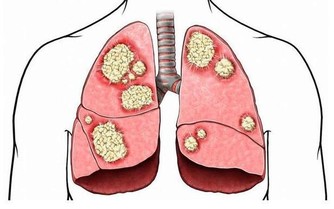

❶ 、【功能主治】養陰清肺,化痰益氣。用於肺熱燥咳、陰虛勞嗽、乾咳痰粘、氣陰不足、煩熱口乾。

❶、【性味】甘苦淡,涼。 ❷、【歸經】 入肺、脾經。 ❸、【功能主治】 養陰清肺,益胃生津。用於肺熱燥咳、勞嗽痰血、熱病津傷口渴。 10石斛

廣告 - 請繼續往下閱讀 ❶、【性味歸經】,味甘,性平。歸肺;胃經。 ❷ 、【功效主治】滋陰潤肺;養胃生津。燥咳;勞嗽;熱病陰液耗傷之咽乾口渴;內熱消渴;陰虛外感;頭昏眩暈;筋脈攣痛。 13陳皮

❶、【功能主治】養陰潤肺,清心安神。用於陰虛久咳,痰中帶血,虛煩驚悸,失眠多夢,精神恍惚。具有養陰潤肺止咳功效,用於肺陰虛的燥熱咳嗽,痰中帶血,如百花膏。治肺虛久咳,勞嗽咯血,如百合固金湯。具有清心安神功效,用於熱病餘熱未清,虛煩驚悸,失眠多夢等。藥用時煎服,10~30g。清心宜生用,潤肺蜜炙用。 ❷、【功效】養陰清熱,滋補精血。 16玉米須 玉米須味甘、淡,性平;歸腎、肝、膽經;質輕滲降;具有利尿消腫,平肝利膽的功效;主治水腫,小便淋瀝,黃疸,膽囊炎,膽結石,高血壓病,糖尿病,乳汁不通。有利尿降壓功能。 廣告 - 請繼續往下閱讀 17紅豆 ❶、【性能】味甘,性平。能健脾利濕,散血,解毒。 ❷、【用途】用於水腫、腳氣;產後缺乳,腹瀉、黃疸或小便不利;痔瘡,腸癰。 18杏仁

富含蛋白質、脂肪、糖類、胡蘿蔔素、B族維生素、維生素C、維生素P以及鈣、磷、鐵等營養成分。其性苦微溫,有小毒,滋潤養肺通便。適用於陰虛肺熱、咳嗽、咽乾舌燥、大便乾結者。 19羅漢果

廣告 - 請繼續往下閱讀 其性甘涼,清熱潤肺止咳通便。 20紫蘇